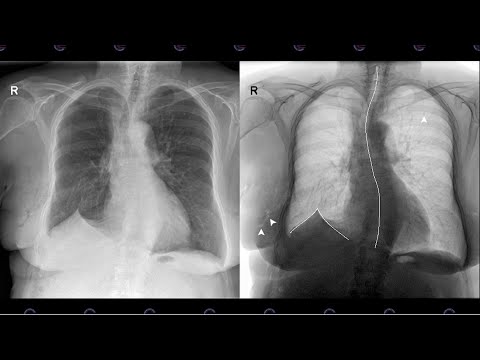

Các xét nghiệm ung thư xương gồm: Chụp X-quang: Phương pháp này cho thấy hình ảnh bất thường của xương mà không cần đến phẫu thuật. Dấu hiệu của ung thư xương có thể là xương không lành lặn, có lỗ tro

Chụp X quang: Thông qua hình ảnh giúp bác sĩ xác định được vị trí ban đầu và chỗ phát triển của khối ung thư. Chụp CT, MRI: Phương pháp này cung cấp được hình ảnh chi tiết để về xương để chẩn đoán chí

Khi chụp XQuang xương có thể thấy hình ảnh tiêu xương, bong màng xương, hình cỏ cháy, hình vỏ hành. Muộn hơn thì có hình ảnh xâm lấn phần mềm. Một số dấu hiệu khác mà bạn có thể nhận biết bệnh ung thư